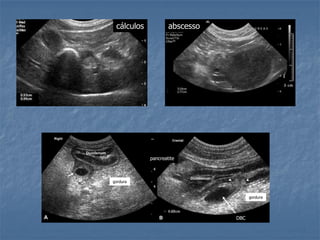

Cálculos

 Raros e nem sempre associados a

presença de sinais clínicos

 Estruturas hiperecogênicas produtoras de

sombra acústica variável

 com ou sem mobilidade

 Obstrução por cálculos em ductos são de

difícil diagnóstico

 Composição: colesterol, bilirrubina, calcio,

magnesio e oxalato

Obstrução Biliar Extra-Hepática (cães)

 Sinais de obstrução

Pesquisa da etiologia da obstrução/ compressão:

- Inflamatória (fígado, pâncreas e TGI)

- Cálculos

- Tumores (fígado, pâncreas, linfonodos, duodeno)

cálculos abscesso

DBC

gordura

pancreatite

colelitíase

colangiocarcinoma

colangite e pancreatiteInflamação pielogranulomatosa com fibrose